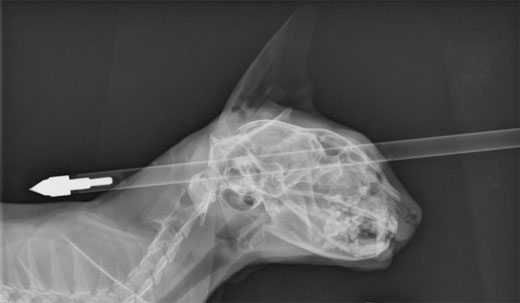

1주 전 무무(Moo Moo)라는 6살 고양이는 두개골에 화살이 꽂히는 사고를 당했다.

고양이 주인 도나 페라리는 다친 무무를 살리기 위해 인근 대학동물병원으로 급히 데리고 갔고 무무는 다행히 응급 수술을 받을 수 있었다.

주치의 조나단 브레이 박사는 “그는 엄청나게 운 좋은 고양이다”면서 “상처는 코와 눈구멍에 약간의 손상만 입은 정도였다”고 설명했다.